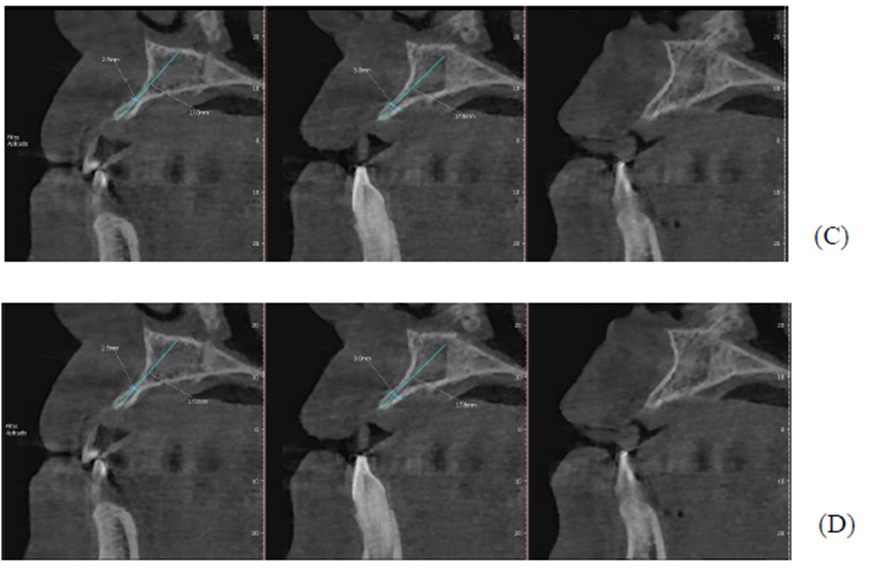

Figuras A,B,C, D e E: imagens evidenciando grande perda óssea anterior no sentido horizontal, bem como a vestibularização do rebordo anterior, o que impossibilita a instalação dos implantes em um bom posicionamento tridimensional.

Após oito meses, foi realizada outra tomografia computadorizada (TC) na própria clínica escola, onde foram realizadas medidas de altura e espessura evidenciando grande ganho ósseo horizontal. Não ocorreu quaisquer tipos de complicação no pós-operatório tardio. (Figuras 1-A, 1-B, 1-C, 1-D).